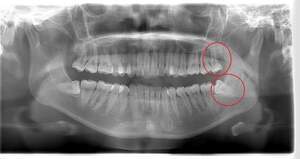

右下の親知らずが疼く症例

- 抜歯前写真(レントゲン)

| 親知らずの生え方 | 横向きに生えている |

| 抜歯内容 | 右下の親知らずは横向きに生えて埋まっているため、麻酔をし親知らずの奥に切開を入れて歯ぐきを開き、歯を囲んでいる骨を削り歯の頭部分を割って出してから、残った根の部分を取り出して抜歯は終了しました。 歯ぐきを切った部分は糸で縫っています。このケースでは根の先端が神経に近く麻痺のリスクがありましたが事前にCTを撮影し、神経との位置関係を確認していたため、麻痺が残ることはありませんでした。 約1週間後に糸取りを行い、その際も多少の痛みや腫れはありましたが後日その痛みも無くなりました。 |